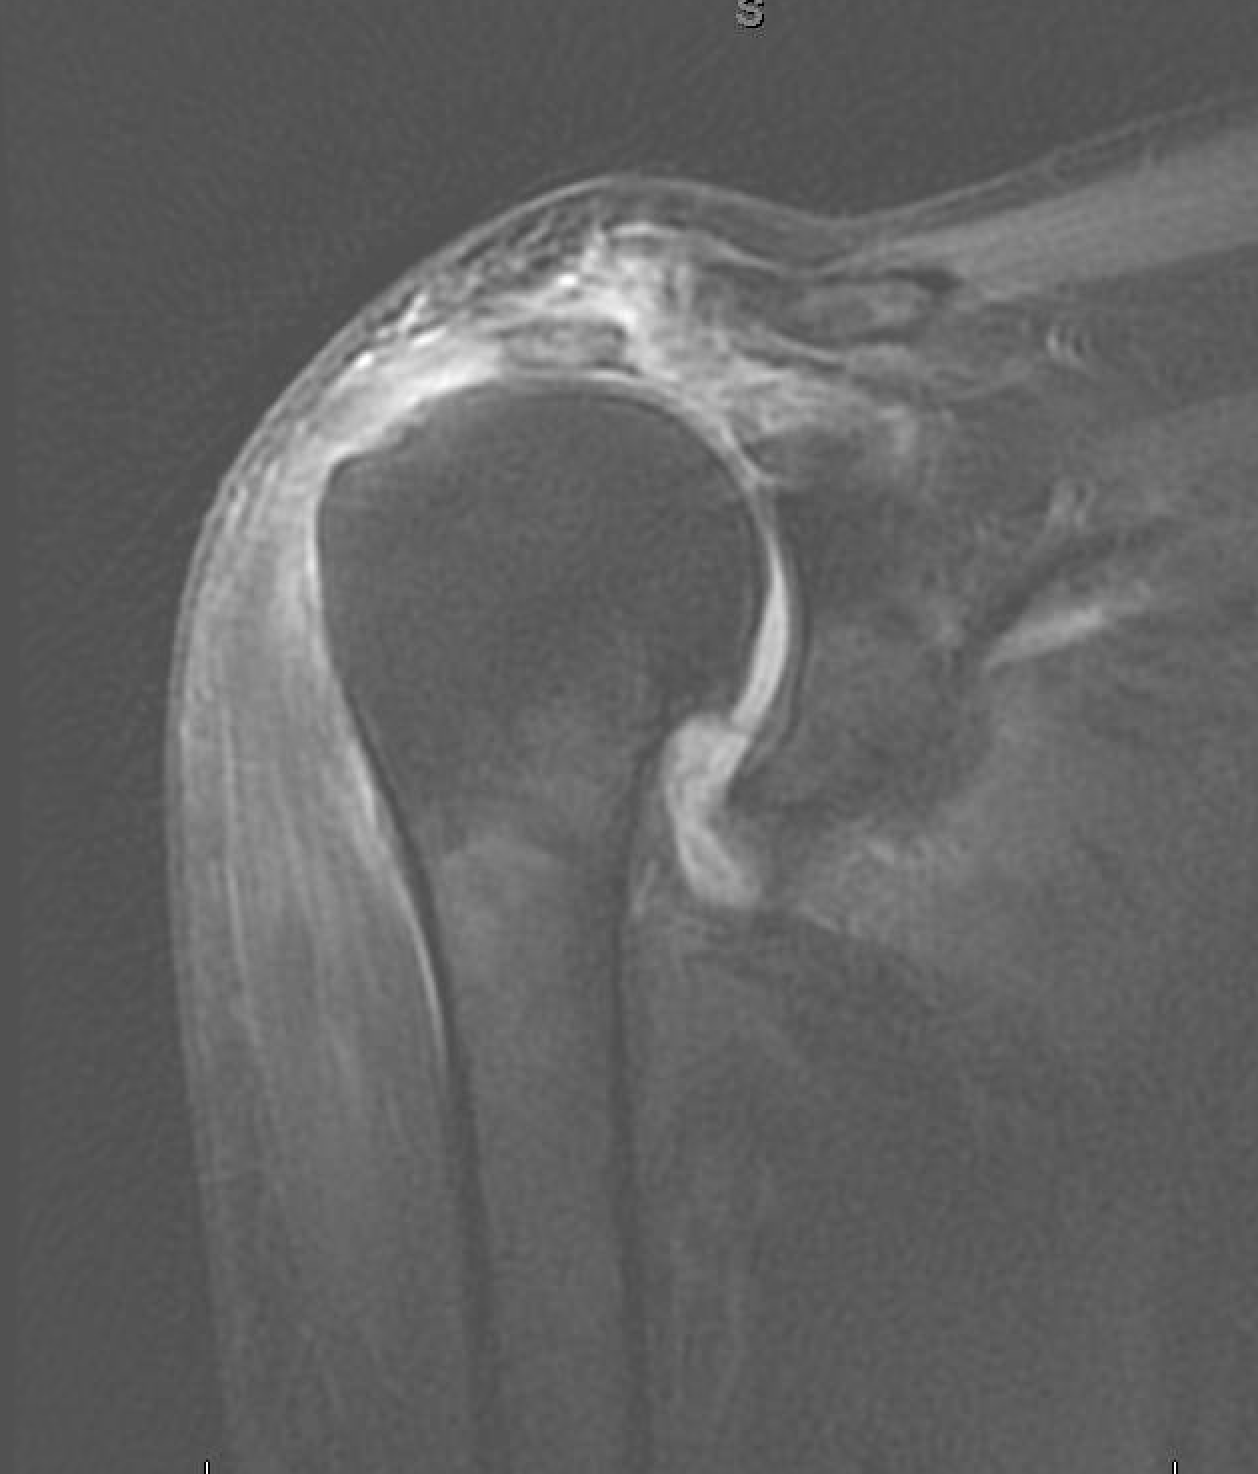

Rotator Cuff Surgery Elderly Patients . With increasing age, the prevalence of rcts also. Rotator cuff tears (rct) are a common clinical problem in the geriatric population, and debate exists over how to best provide pain relief and. Our results showed that statistically and clinically significant rom and cms recovery and a rotator cuff integrity rate of 75% can be. Rotator cuff tears (rcts) are a common cause of pain and shoulder dysfunction (1, 2). In 2004, frankle et al. Rotator cuff repair in patients aged >75 years could achieve high clinical success rates with good outcomes and pain relief. Michael stone followed 83 patients 75 years or older for five years following arthroscopic rotator cuff repair. Rotator cuff tears (rct) are a common clinical problem in the geriatric population, and debate exists over how to best provide pain relief and.